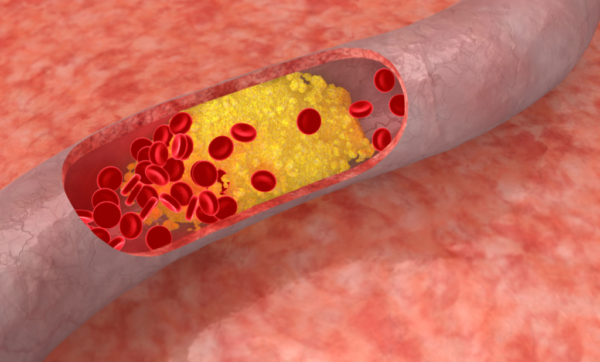

La ateroesclerosis, proceso de daño progresivo de los vasos arteriales dependiente de la edad, puede alterar el flujo sanguíneo coronario y provoca isquemia e infarto. Se presenta cuando se acumulan grasa, colesterol y otras sustancias en las paredes de las arterias. Estos depósitos se denominan placas. La ateroesclerosis a menudo ocurre con el envejecimiento. A medida que se envejece, la acumulación de placa estrecha las arterias y las hace más rígidas. Estos cambios dificultan el flujo de sangre a través de ellas.

La ateroesclerosis produce bloqueos parciales o completos, por formación de placas ateroescleróticas constituidas por lipoproteínas, células inflamatorias y tejido conjuntivo. Las placas ateroescleróticas pueden romperse, provocando trombosis y oclusiones arteriales, causantes de infarto de miocardio, accidente cerebrovascular isquémico, y enfermedad arterial periférica.

La ateroesclerosis causa un 90% de los casos de infarto de miocardio y el 60% de los accidentes cerebrovasculares.

Habitualmente, el proceso ateroesclerótico no da síntomas durante meses, años e incluso décadas, y es posible que nunca genere manifestaciones clínicas. No obstante, si la superficie de la placa resulta dañada, puede producirse una oclusión trombótica de la arteria. Los trombos ateromatosos aumentan de tamaño rápidamente y pueden ocupar la luz en el plazo de minutos, lo que ocasiona isquemia e infarto.